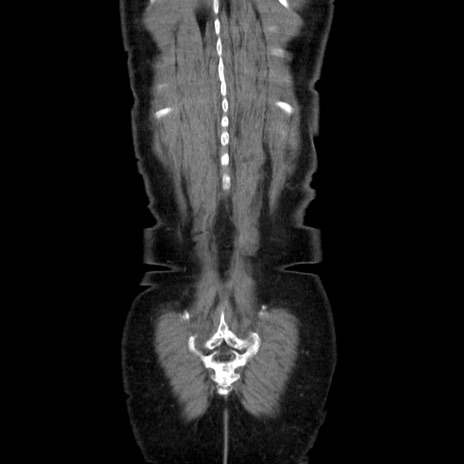

症例5(冠状断像)

【症例】70歳代女性

【主訴】お腹が張る

【現病歴】1週間くらい前から腹部膨満の自覚あり。昨日夜から増悪したため、本日救急外来受診。

【身体所見】意識清明、BT 36.5℃、BP 165/106mmHg、HR 80bpm、SpO2 98%、腹部:膨満、軟、自発痛・圧痛なし、触診にて不快感あり、腸蠕動音:減弱

【データ】WBC 12600、CRP 1.04